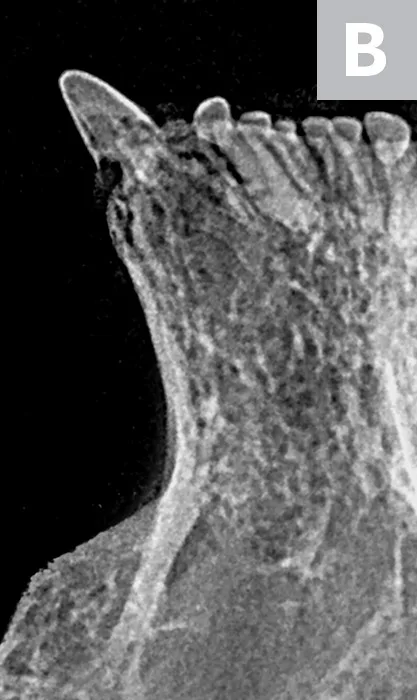

Tooth resorption type is determined via intraoral radiography based on root opacity and periodontal ligament space (see Types of Tooth Resorption Based on Radiographic Appearance and Figure 2).

Radiograph of a left mandibular molar tooth in a cat with Type 1 resorption (A) in which focal or multifocal radiolucency can be seen with otherwise normal radiopacity and normal periodontal ligament space. Radiograph of mandibular incisors and canine teeth in a cat with Type 2 resorption (B; white arrow) in which narrowing or disappearance of periodontal ligament space is present in at least some areas, and part of the tooth demonstrates decreased radiopacity. Radiograph of the right maxillary third and fourth premolars in a cat with Type 3 resorption (C); the third premolar features Type 1 resorption of the mesial root (arrowhead) and Type 2 resorption of the distal root (dashed arrow) with exposure to the oral cavity.

Type 1 (T1): focal or multifocal radiolucency in a tooth with otherwise normal radiopacity and normal periodontal ligament space

Type 2 (T2): decreased radiopacity in part of a tooth with narrowed or absent periodontal ligament space in at least some areas

Type 3 (T3): features of Type 1 and Type 2 in the same tooth; focal or multifocal radiolucency in a tooth and decreased radiopacity in other areas of the tooth with areas of normal and narrow or lost periodontal ligament space